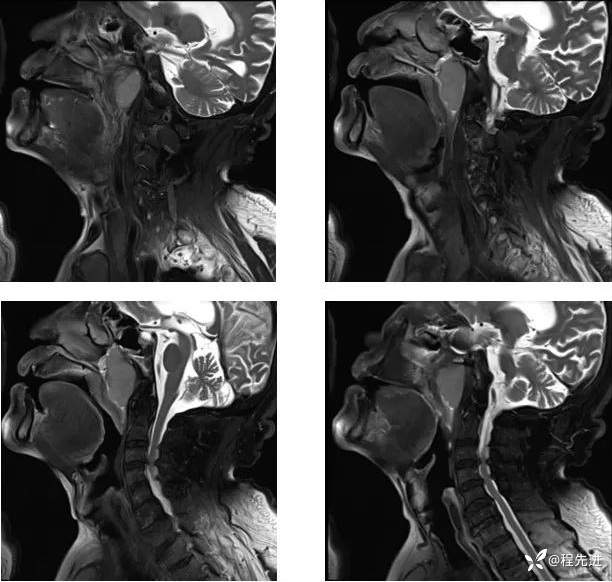

MR平扫+增强:

DWI、ADC: